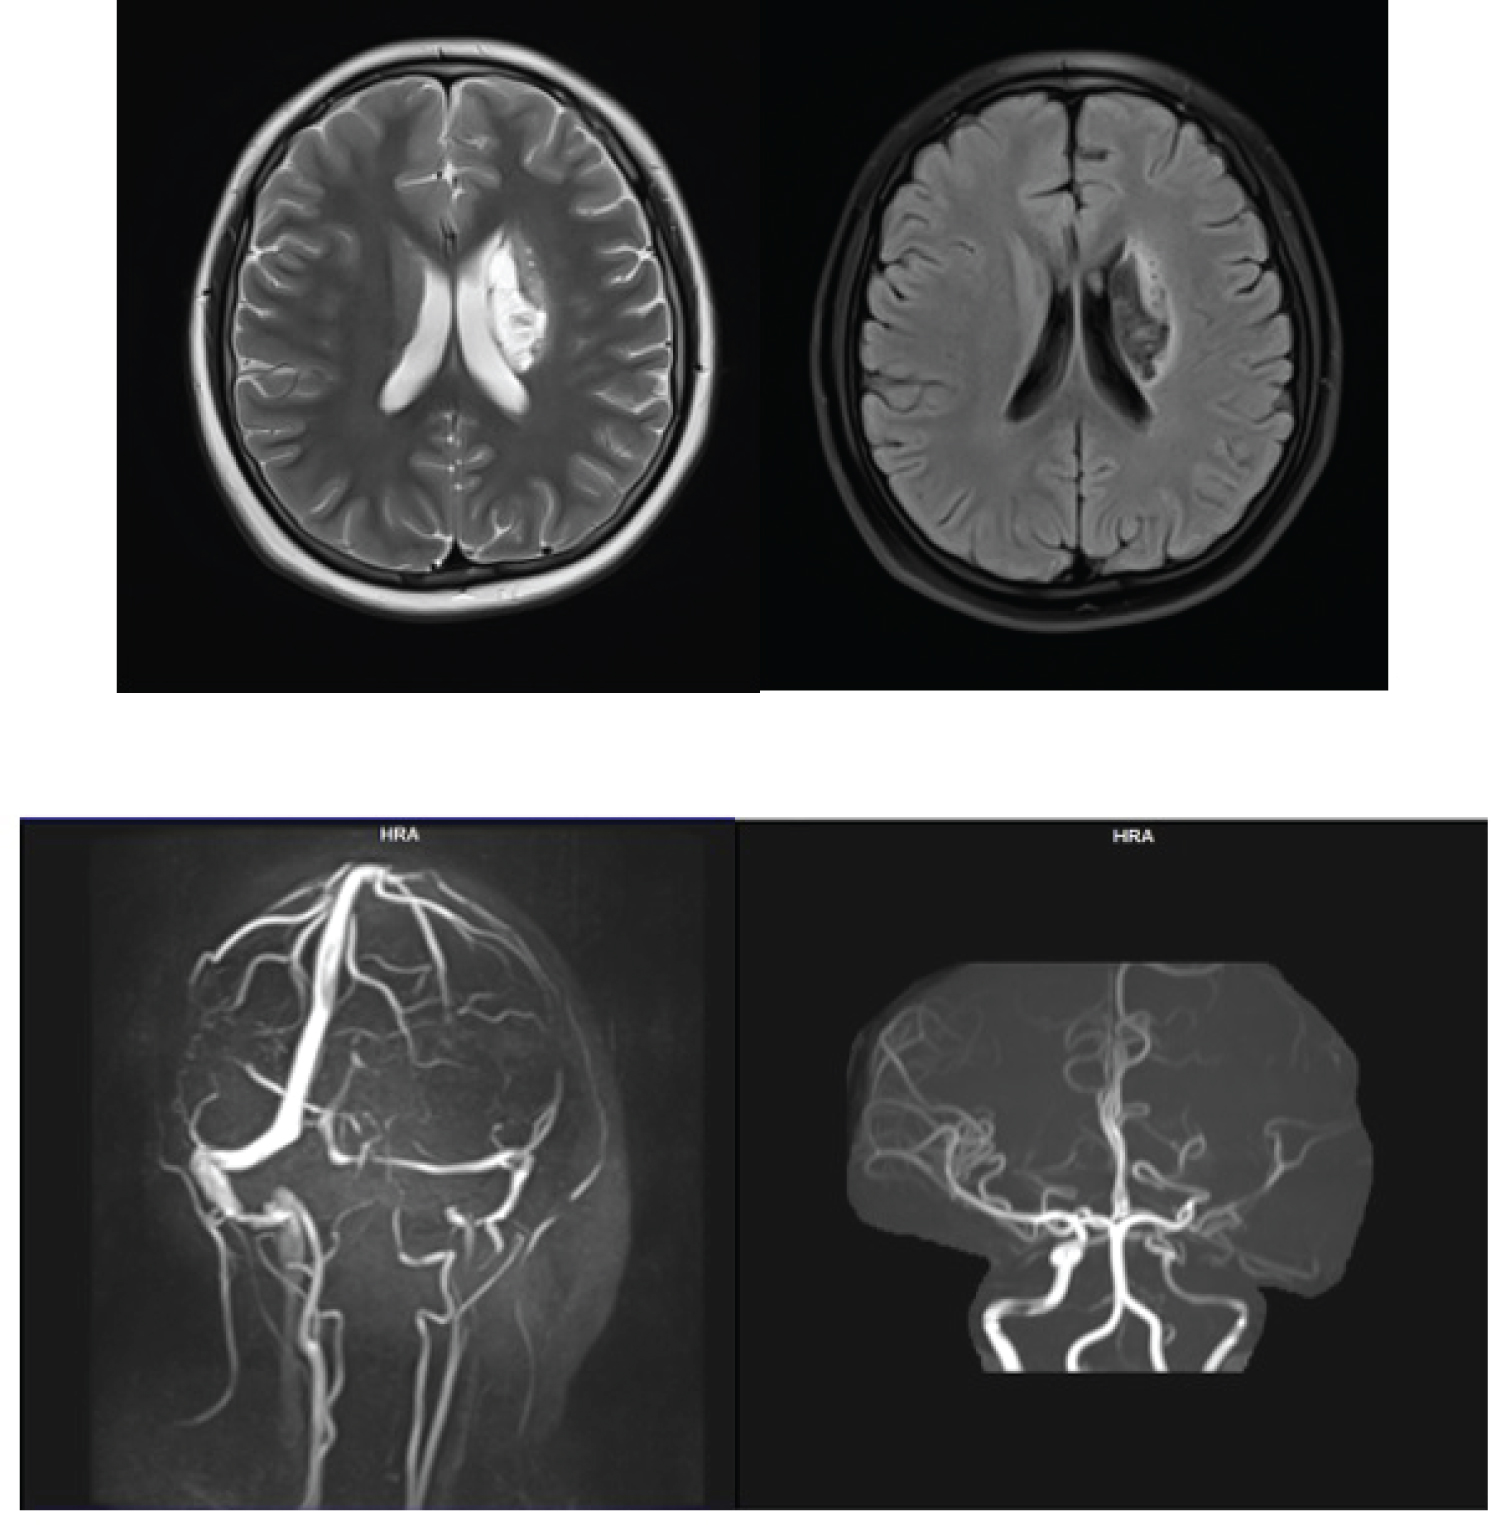

Brain MR was performed, and we found chronic infarct area in the right base of ganglia and right lateral periventricular, hemorrhagic lesion was not found. MRA and MRV showed brain vessels within normal (Figure 5).

Figure 5: Brain MR imaging (a) FLAIR sequence with infarct lesion in right base of ganglia and lateral periventricular; (b) MRV and MRA imaging within normal. View Figure 5

Elective Cerebral Digital Subtraction Angiography followed by Intra Arterial Heparin Flushing (IAHF) was performed. After this treatment, we found direct improvement in left sided motor function. He was able to raise his left hand over his ear, his hand grips strength improved, and finger foot flexion a left foot plantar flexion was reduced. After 4 hours of observation, we performed perfusion MRI to compare brain perfusion before and after IAHF. Compared to pre-IAHF, we found increasing perfusion in cortical and subcortical area (Figure 6).